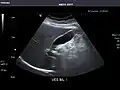

Left kidney -

Kidneys: Right and left kidneys measure 11.5 cm and 12 cm in length respectively. No hydronephrosis. Small left lower pole kidney cyst.